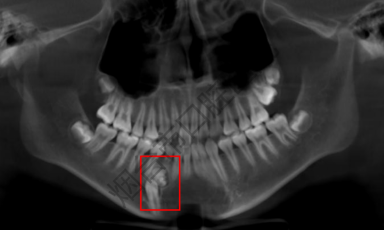

近日,12岁的男孩林林(化名)因为要做牙齿正畸来到烟台市口腔医院就诊。医生在常规检查时发现,他右下颌的一颗乳牙迟迟没退,属于乳牙滞留的情况。为了查清楚原因,医生安排他做了CBCT检查,这一查竟发现了大问题——林林的颌骨里藏着一个边界清晰的“团块”,里面密密麻麻裹着十几颗形态各异的“小牙”。

据了解,林林在此前一个月内并未感到任何疼痛或不适,这个“藏”在骨头里的“小麻烦”,全靠检查才被发现。结合检查结果,医生初步判断这是“牙瘤”,随后安排林林住院治疗。